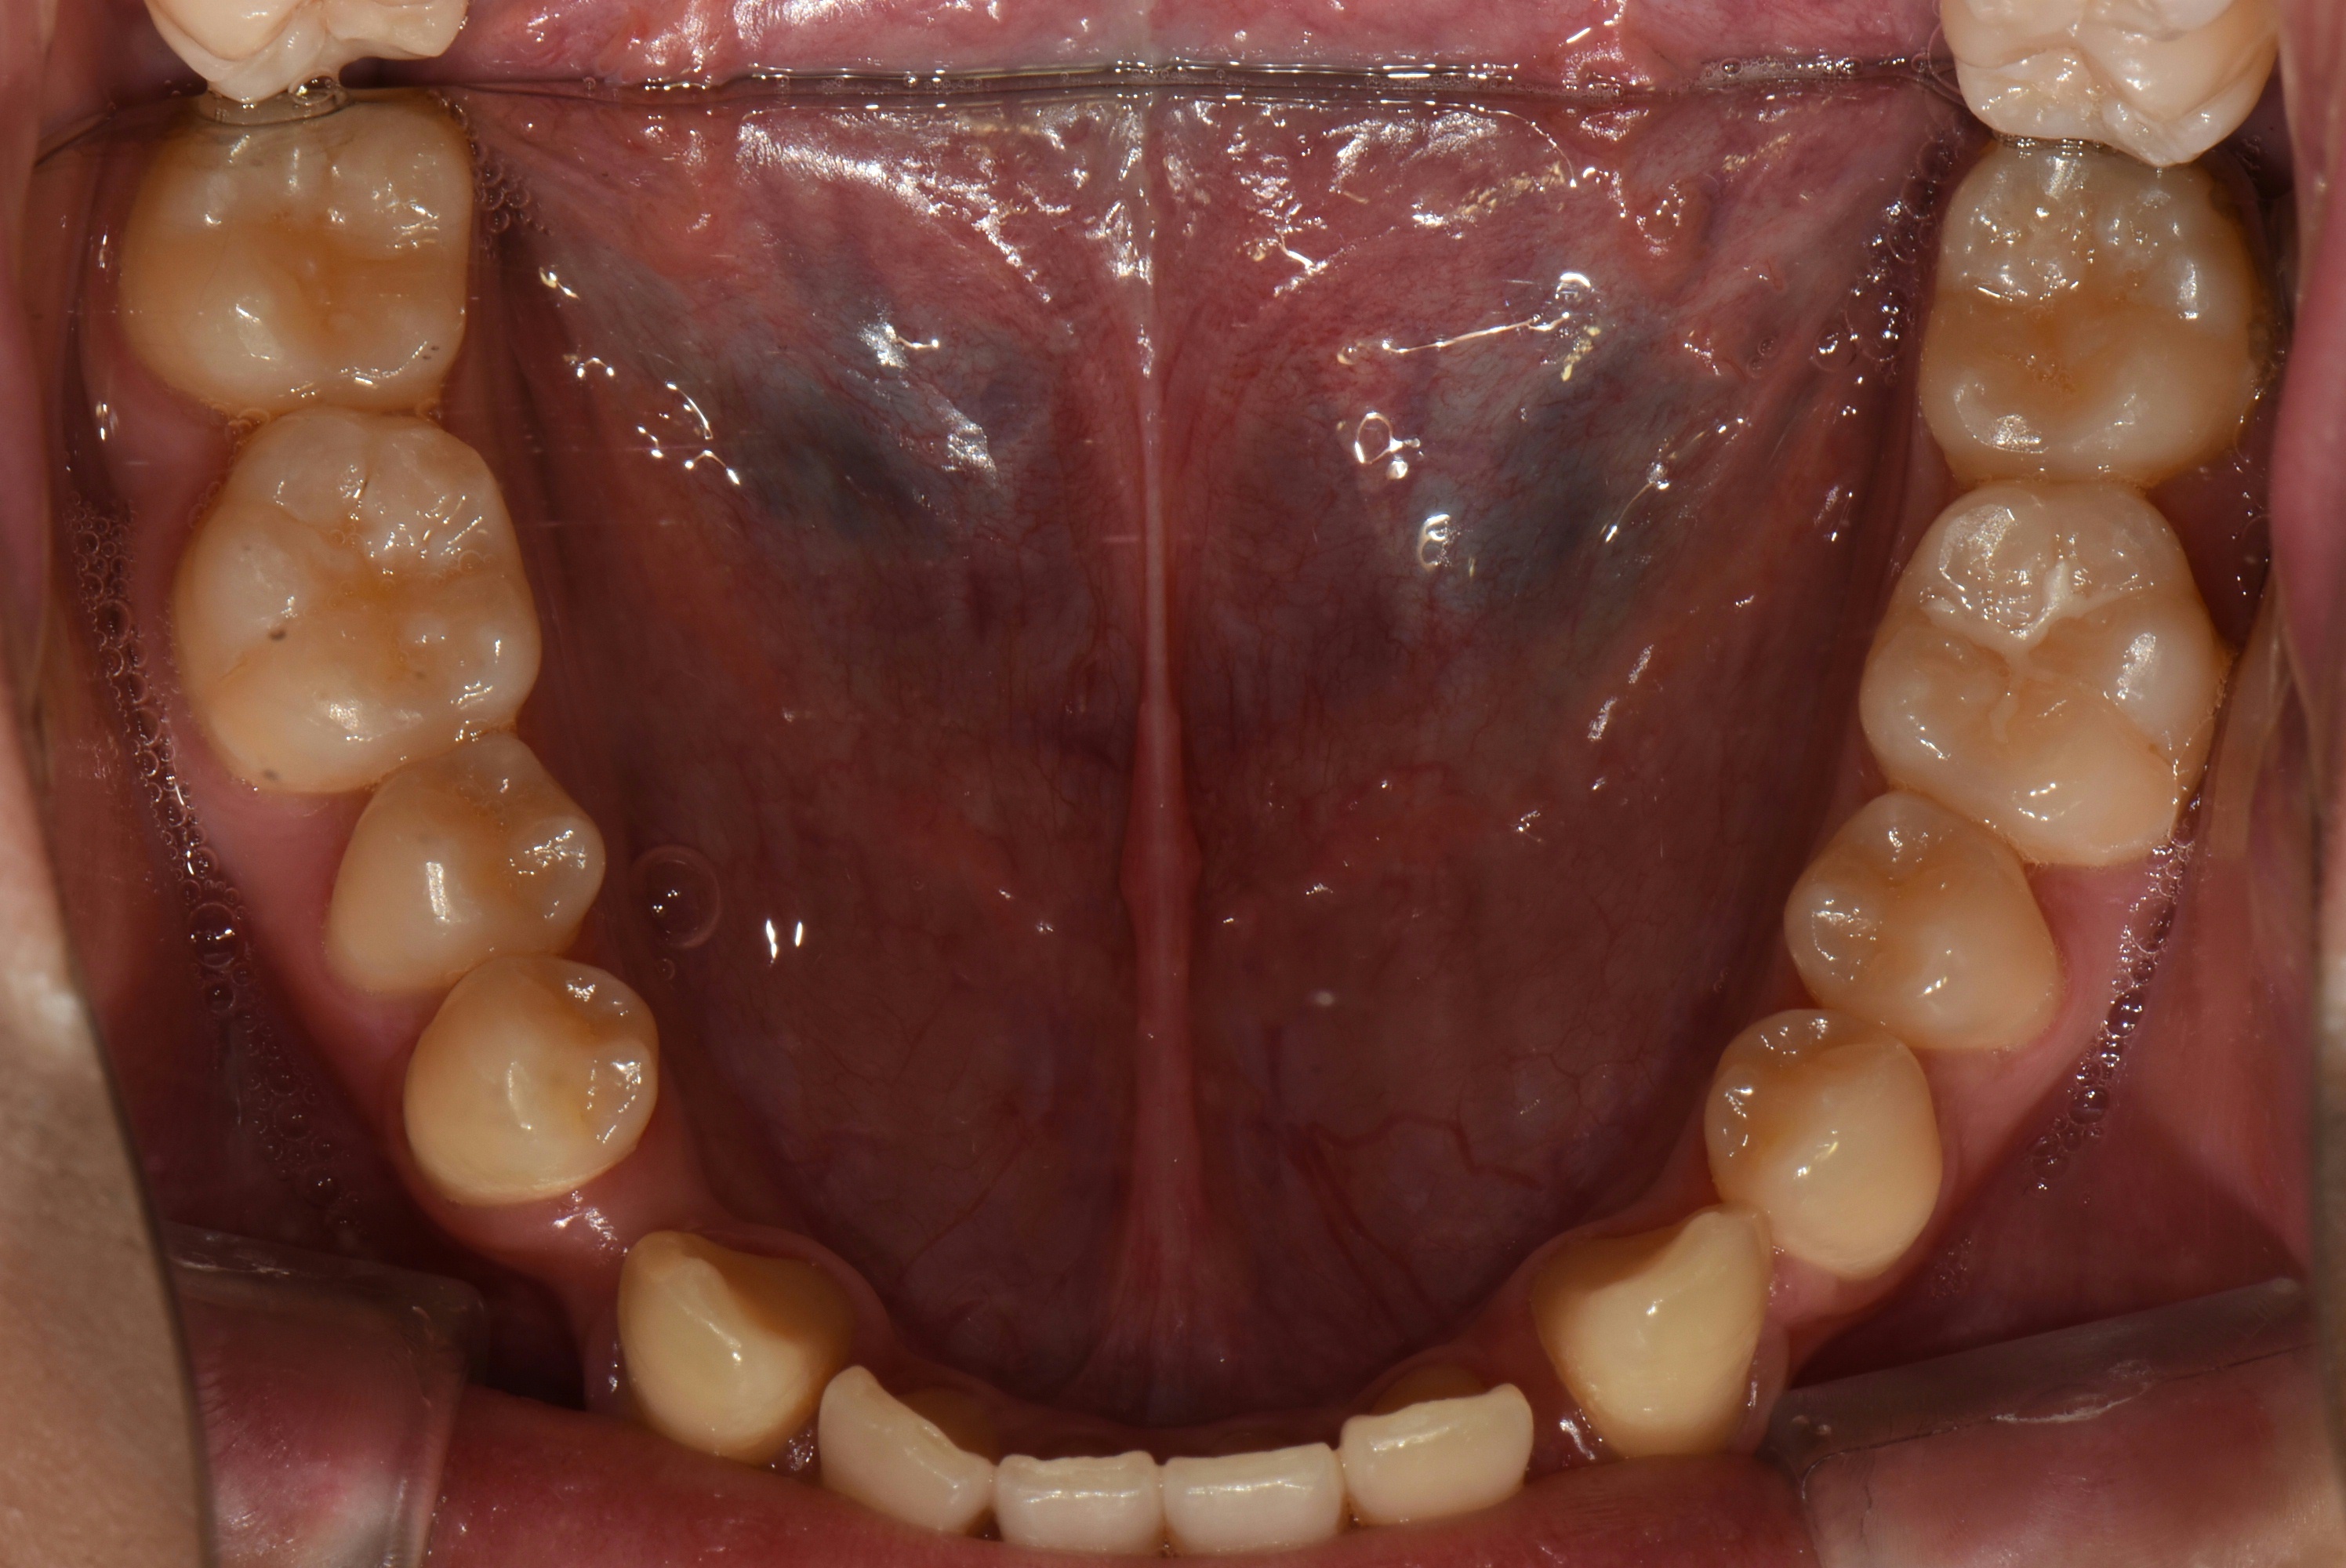

치료 전 사진입니다.